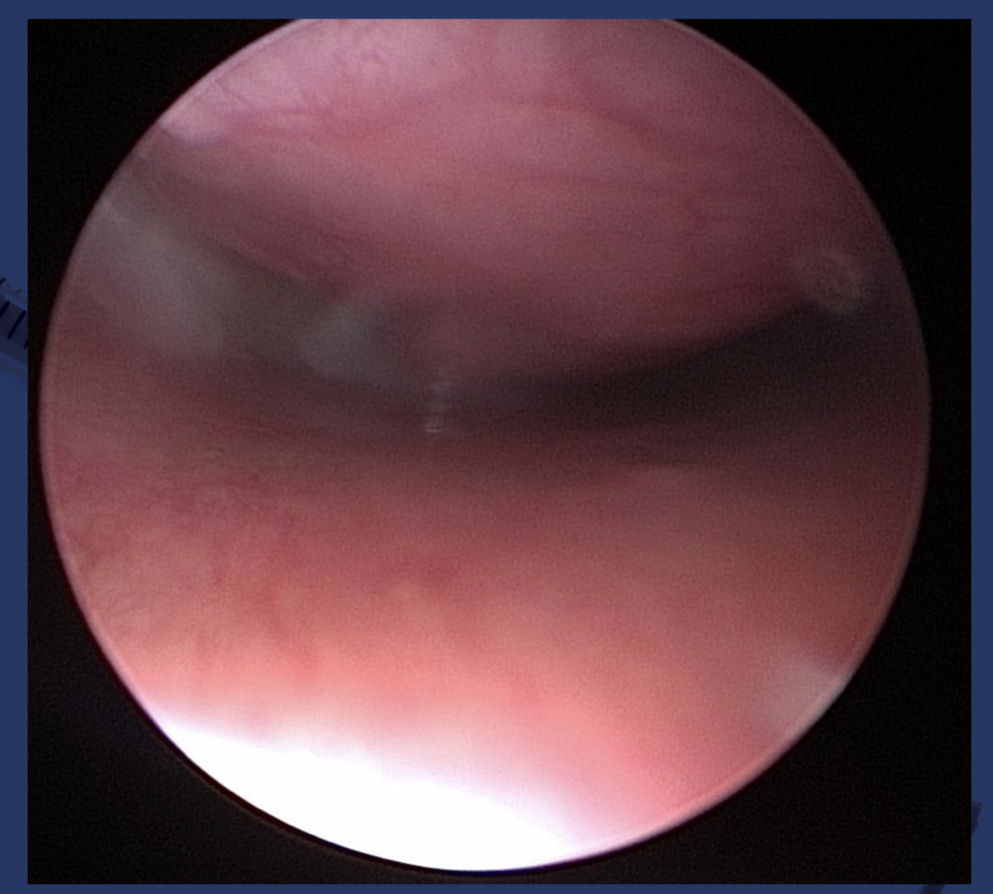

What are the 4 grades of tracheal collapse?

1. tracheal membrane is slightly pendulous, cartilage remains normal, and lumen is reduced 25%

2. tracheal membrane is widened and pendulous, cartilage is partially flattened, lumen is reduced 50%

3. tracheal membrane is almost in contact with dorsal trachea, cartilage is nearly flat, lumen is reduced 75%

4. tracheal membrane is lying on the dorsal cartilage, cartilage is flattened and may invert, lumen is obliterated

does not seem to relate to clinical signs